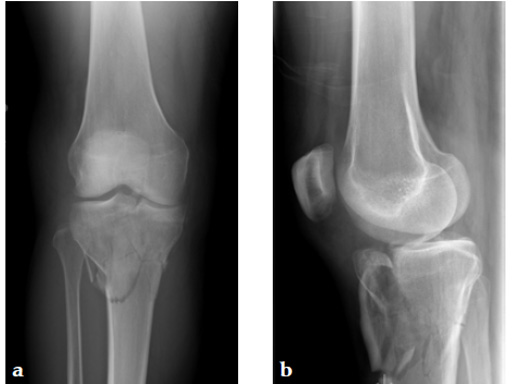

A 36-year-old man sustained a motorcycle injury: right femoral shaft fracture and right hyperextension bicondylar tibial plateau variant (Fig 1, Fig 2).